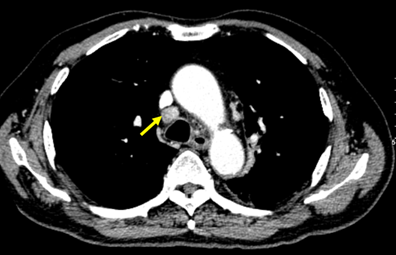

- Chụp cắt lớp vi tính ngực (tháng 9/2024)

Hình 1: U trung tâm phổi trái (vòng tròn đỏ) kích thước 72*41mm trên của sổ nhu mô và cửa sổ trung thất

Hình 7.1: Cắt lớp vi tính ngực ở cửa sổ nhu mô

Hình 7.2: Hình ảnh cắt lớp vi tính ngực ở cửa sổ trung thất

Kết luận: Hình ảnh chụp cắt lớp vi tính ngực: sau 6 đợt điều trị khối u (vòng tròn đỏ) giảm kích thước từ 72x41mm (bên trái) xuống còn 43x28mm (bên phải)